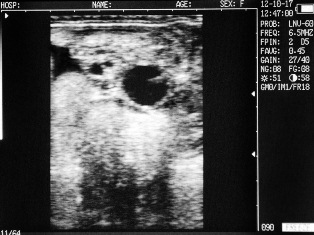

Ultrasound images of cows reproductive system, generated by a scanner Sonovet with rectal linear transducer.

Ovary cows in mid-cycle